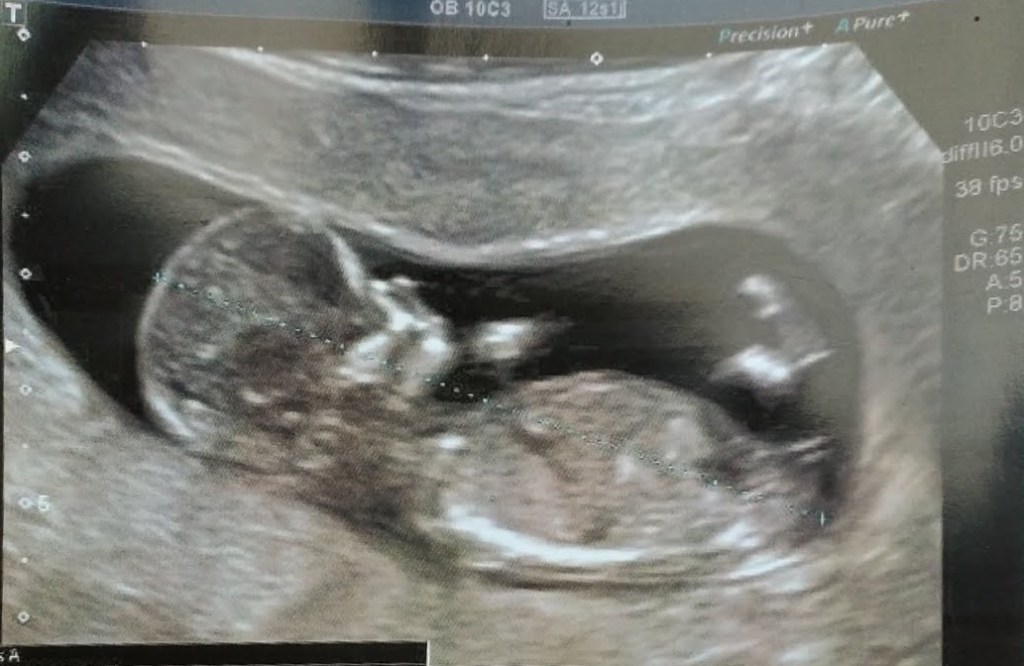

It’s the next day and I’m waiting for my husband to arrive, the nurses came into the room and wheel me down to check if the baby is still breech, she’s still in her cozy spot under my ribs, I’m wheeled back to my room and told to shower with Betadine.